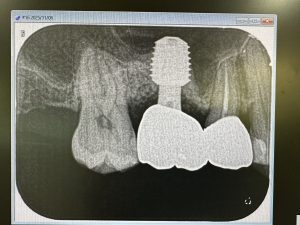

3年前にオペしたソケットリフト

異物の人工骨は一切使わずに、自己採血より得られた濃縮血漿板のみでの挙上

骨も緻密化され非常に安定している、手前5番の膜も安定、PT値もマイナス4